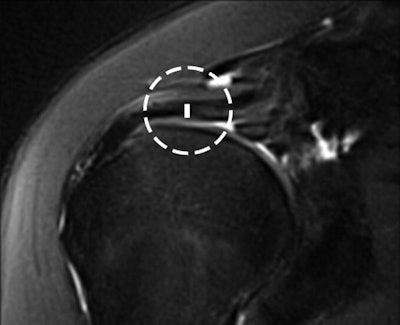

The rotator cable was visualized in 74% of the MRI studies on both coronal and sagittal oblique sequences by both readers. The mean width of the cable was 1.24 ± 0.31 cm and the mean thickness was 0.19 ± 0.05 cm.